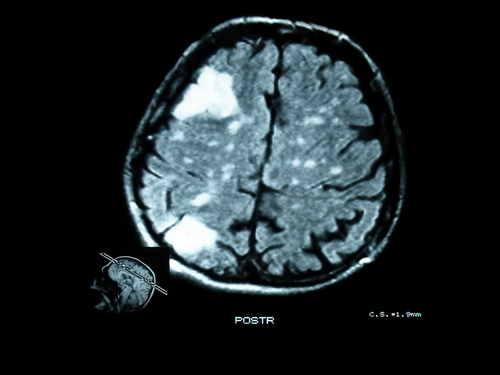

Some of the really helpful insights in this book are the case studies of people who have brain damage to one of their hemispheres. “An inability to recognise faces is called prosopagnosia, and follows right-hemisphere lesions” (p. 60). The left hemisphere see things in parts whereas the right hemisphere sees the whole. So when the right hemisphere is damaged, and the left is on its own, it tries to recognize a face part by part, the nose, the eyes, the shape of the chin, and struggles to recognize a face. The right sees the whole and has no trouble.

The right hemisphere has a closer physiological relationship with the body. McGilchrist notes that parents, going back thousands of years, tend to hold infants to the left side of their body – this puts them in the direct line of sight of the left eye which is connected to the right hemisphere. [This is a bit confusing: the right side of our body, including eyes, corresponds to our left brain hemisphere, and vice versa]. In patients with right hemisphere damage, such as a stroke, “there appears to be a removal of the normal integration of self with body: the body is reduced to a compendium of drives that are no longer integrated with the personality of the body’s ‘owner.’ This can result in a morbid and excessive appetite for sex or food, which is out of keeping with the nature of the individual involved” (p. 69).